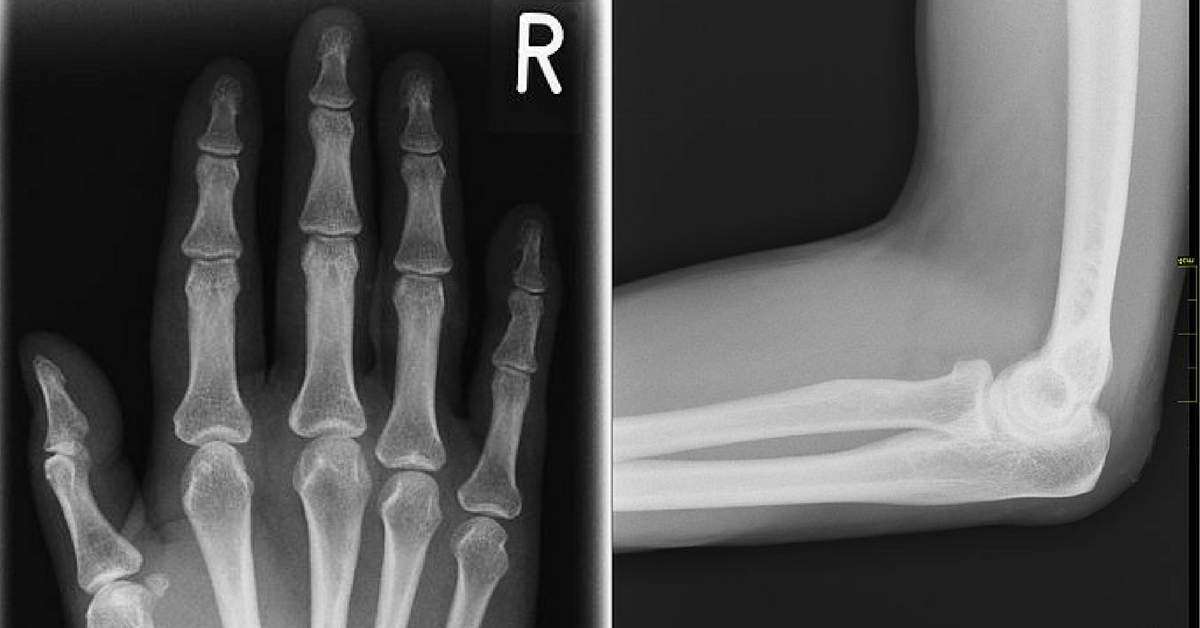

Knocking your funny bone on something certainly isn’t laugh-out-loud funny. The name references another kind of funny: You feel funny when it happens—a specific kind of jolting nerve pain that spreads throughout the whole body for just a second. (The common phrase “Tickle your funny bone” just complicates things unnecessarily.) Oh, and the funny bone isn’t really even a bone. Hitting it on a wall or door sends weird (okay, funny) nerve pain throughout the body because it is a nerve. It’s the ulnar nerve, and the pain comes from it getting pinched under a bone. And that bone is the long, elbow-to-shoulder spanning one called the humerus, pronounced humorous, which could also be why the funny bone is called what it is.

Pinky